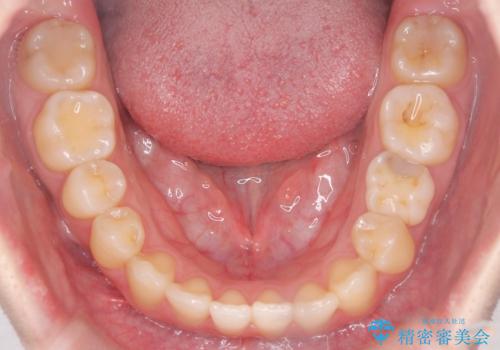

- 前歯の捻れを主訴に来院されました。

インビザラインを希望されておりましたが、20時間もつけることができなかったためワイヤー矯正にて叢生の改善を行っています。

右上の側切歯(前から2番目の歯)が90度程度ねじれている状態でしたが、1月に1回のワイヤー交換できれいに並ぶことができ満足いただけました。

捻れた歯の治療に関しては、ワイヤー矯正の方が仕上がりがきれいに治りやすいです。